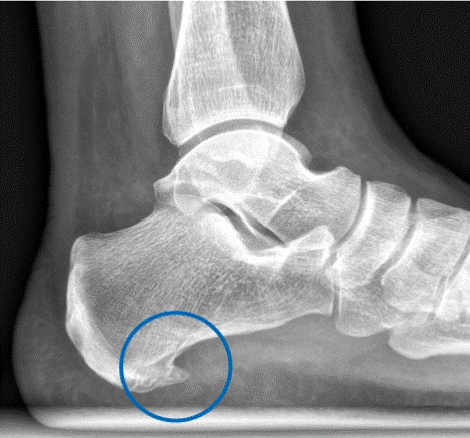

Dolor de talón neuropático: nervio de Baxter

El dolor de talón es una de las consultas más frecuentes tanto en fisioterapia como en podología. Si bien suele relacionarse con la fascitis plantar, existe una causa menos conocida que puede pasar desapercibida: la neuropatía del nervio de Baxter. Este nervio, cuando se ve comprimido, puede generar un dolor punzante en el talón que […]